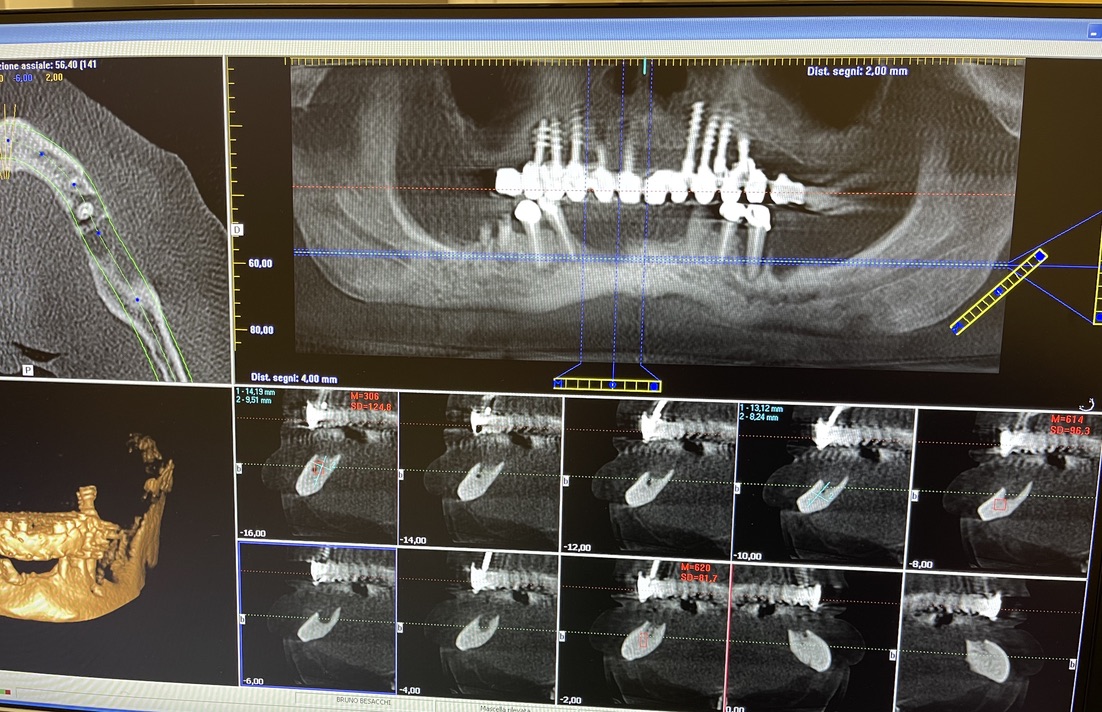

CLINICAL CASE combined with news n.6. Rehabilitation of 04/28/2021

In particular, I consider the following aspects to be significant:

• 5 Presence of implants in the tuber / pterygoid area

• 6 Presence of ancient inclined implants

• 7 Presence of implant bent in 25. (To parallelize it)

• 8 Presence of two mini-plants in 11-12

• 9 Presence of a welded bar in the upper sector

• 10 Severe periodontal disease of the lower sector

The images provide additional information in the captions.